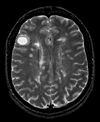

Registration Results

Unregistered baseline data: PD vs. T1Gd Unregistered baseline data: PD vs. T1Gd

Unregistered followup data: PD exam 2 vs. exam 1 Unregistered followup data: PD exam 2 vs. exam 1

Registered baseline data Registered baseline data

Registered followup data Registered followup data

Lesion change visualization in 3DLesion change visualization in 3D

Lesion change via subtraction imaging of co-registered PDLesion change via subtraction imaging of co-registered PD